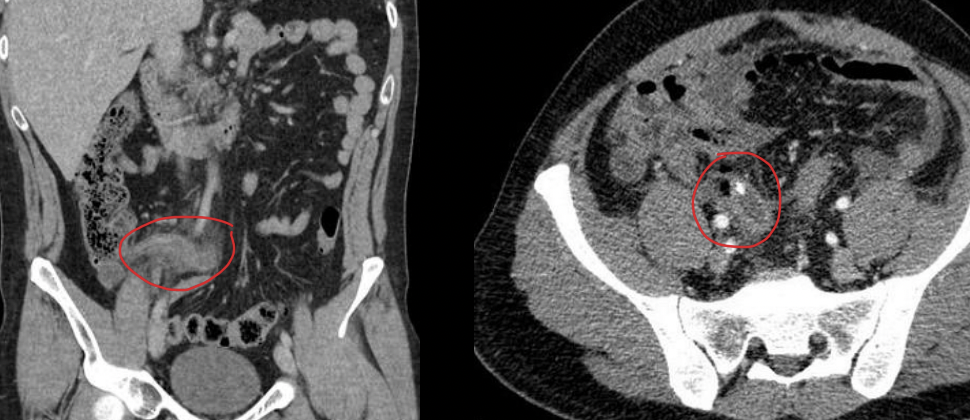

Mejor método dx adultos

TC

APENDICE RETROCECAL

SE VE GRASA SUCIA, APENDICOLITO, REALCE CON CONTRASTE